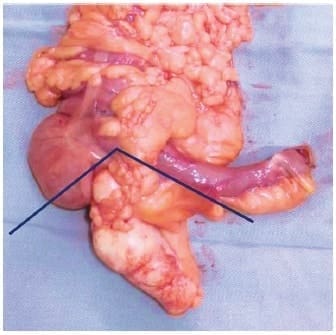

En el 2017, los doctores González-Moreno y Sugarbaker describieron una técnica quirúrgica para el manejo del apéndice cecal en caso de una neoplasia apendicular de tipo epitelial (mucinosa), en la que se recomienda la inclusión del mesoapéndice desde el origen de la arteria apendicular, el borde antimesentérico del ligamento de Tréves y la base apendicular libre que puede incluir el ciego (cequectomía) (Figura 1).

Figura 1. Apendicectomía radical. Incluye base apendicular libre (cequectomía si es necesario),

mesenterio apendicular desde la emergencia de arteria apendicular y el borde antimesentérico

del ligamento de Tréves.

Foto: Autores.

Se enfatiza en la suficiencia de esta técnica para cumplir los objetivos de la cirugía primaria en estos pacientes14.